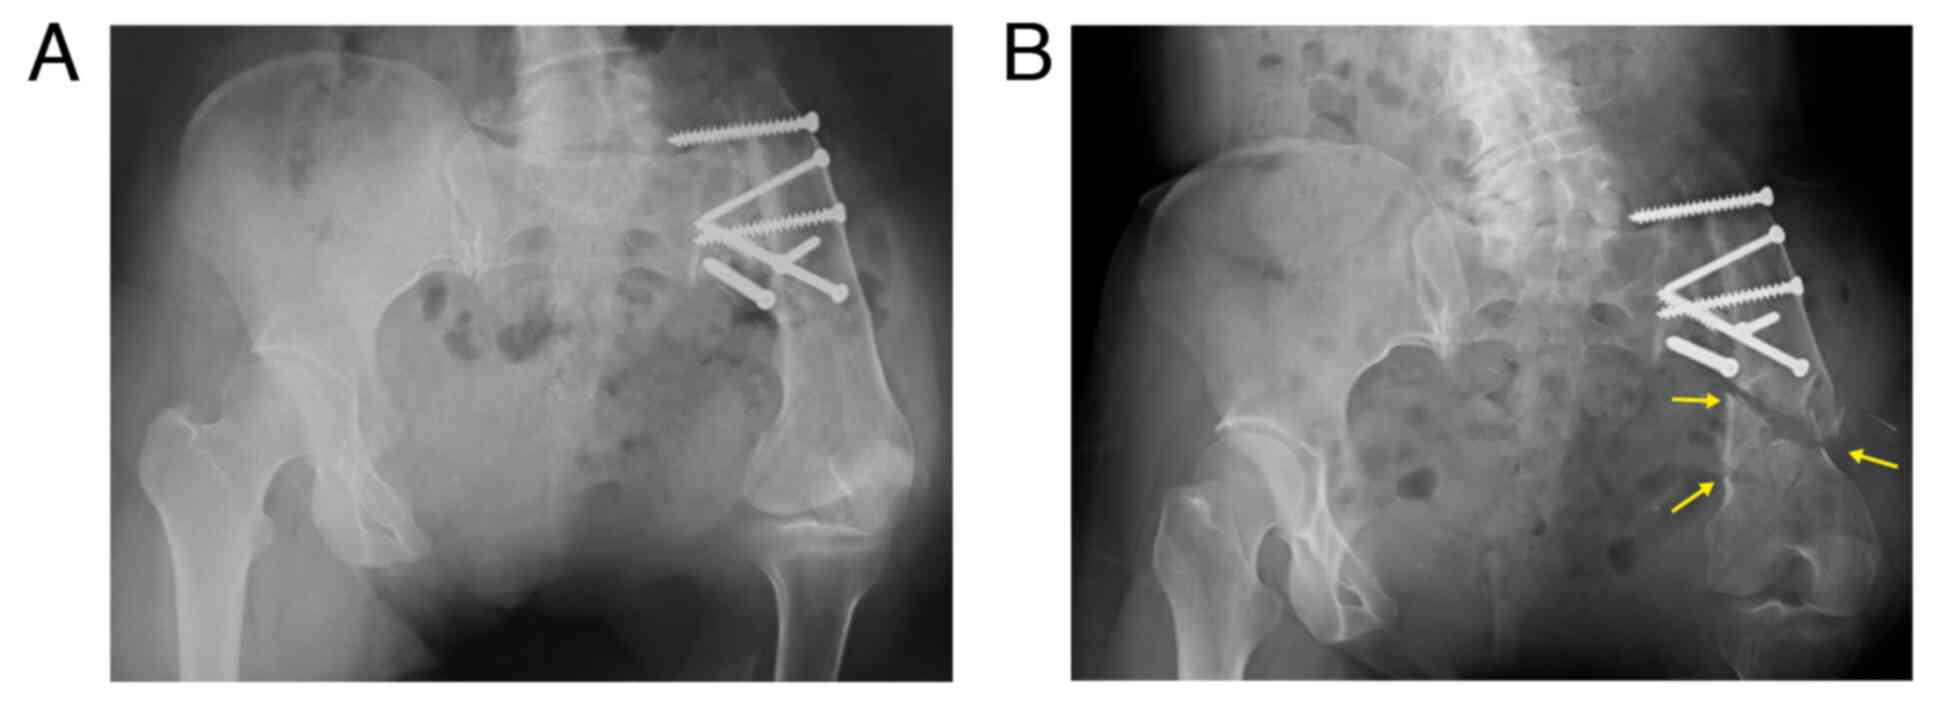

Reconstructed bone fracture 28 years after hip rotationplasty for Ewing sarcoma: A case report

Hip rotationplasty is a surgical method used to treat malignant tumors of the proximal femur. A 52‑year‑old woman, who underwent hip rotationplasty for Ewing sarcoma of the proximal left femur at the age of 24, fell and hit the left buttock. The patient was then admitted to the Department of Orthopedic Surgery, Graduate School of Medicine, University of the Ryukyus. Radiography and computed tomography (CT) revealed a comminuted fracture of the reconstructed bone distally. The patient underwent open reduction and internal fixation (ORIF) and external fixator. External fixation was removed 1 month after the surgery. At two years after surgery, at the latest follow‑up, bone union was confirmed by 3‑dimensional CT. The combination of ORIF and temporal external fixation was effective for the reconstructed bone fractures after hip rotationplasty.

Figure 1

Figure 2